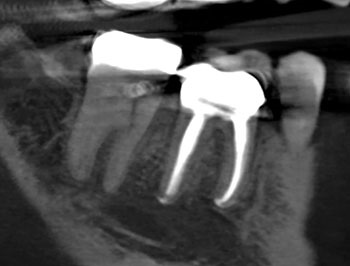

Fig. 2: Postoperative PA.

After the buildup and root-filling material were removed, a microscope was used to confirm that no cracks were present in the pulp chamber or the coronal third of the canals. This tooth was treated in multiple visits using calcium hydroxide, an antimicrobial intracanal medicament, and to confirm healing. The root canal system was cleaned, calcium hydroxide was placed, and a double-layered long-term provisional restoration made of Cavit and bonded composite were placed to seal the access preparation.

The patient returned in three months, when resolution of symptoms, healing of the deep probing defect and bone regeneration were confirmed. The tooth was obturated, and a foundational restoration was placed before the rubber dam was removed. Fourteen years of follow-up confirmed long-term periradicular health. The amount of appreciation and gratitude that this patient expressed reminds us that each individual tooth demands our best efforts.